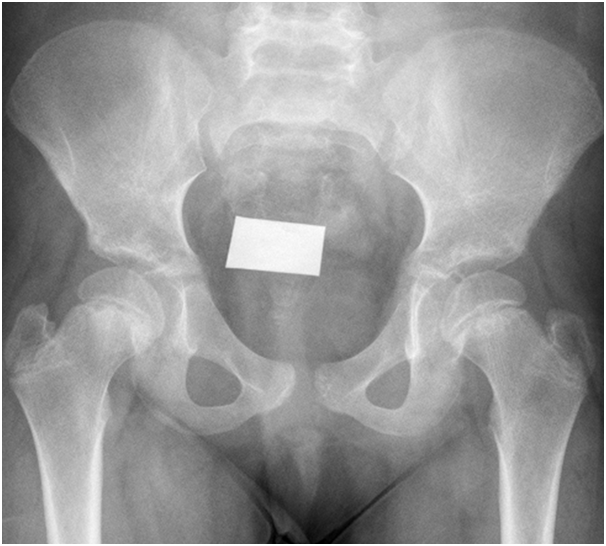

She has tiredness and fatigue and non-specific symptoms. She was treated with thyroxin and her thyroid functions test normalized in 2months time. After her improvement of thyroid functions test she developed limping and pain in her left leg which get worse with activity. We tested her bone profile and we found vitamin D deficiency so she received treatment for that. But in spite of improvement of the vitamin d deficiency and thyroid disease she continue to have the limping and pain in her leg so we referred her to orthopedics. The orthopedic did for her pelvic AP x-ray and found Bilateral symmetrical slipped capital proximal femoral epiphyses are noted with metaphyseal sclerosis and irregularity. The proximal femoral epiphyses are of normal density and contour Unremarkable acceptable in both sides. So she was treated surgically and cannulated screw fixation was done in both hip joints. After that the patient improved regarding limping and pain and without complaints.

In this case we present that after treatment of the sever hypothyroidism the symptoms of masked SCFE appears indicating that evaluations of thyroid function test is strongly recommended in cases of SCFE (Figures 1‒3).

Figure 2 Slipped capital femoral epiphysis in 10years old girl.